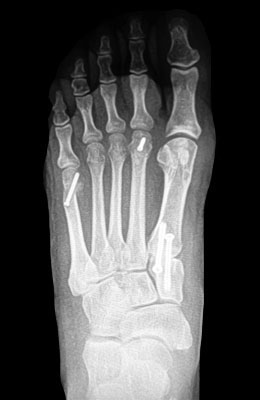

Minimally Invasive Bunion Surgery featuring the CrossRoads miniBunion™ System

Eva is a 24-year-old female who had just began working at a job that required high fashion shoes. She was in constant pain but could not take time off work. Our miniBunion™ Minimally Invasive Bunionectomy allowed her to continue to work and be on her foot with full recovery and return to regular shoes by 6 weeks. She had an amazing range of motion, no more bunion pain, and absolutely no visible incision. After picture taken six weeks post-surgery.